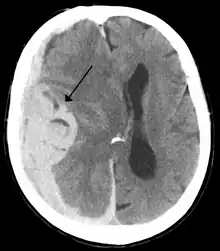

Midline shift (arrow) is present in this brain after a stroke (infarct depicted in shaded area).

Midline shift is a shift of the brain past its center line.[1] The sign may be evident on neuroimaging such as CT scanning.[1] The sign is considered ominous because it is commonly associated with a distortion of the brain stem that can cause serious dysfunction evidenced by abnormal posturing and failure of the pupils to constrict in response to light.[1] Midline shift is often associated with high intracranial pressure (ICP), which can be deadly.[1] In fact, midline shift is a measure of ICP; presence of the former is an indication of the latter.[2] Presence of midline shift is an indication for neurosurgeons to take measures to monitor and control ICP.[1] Immediate surgery may be indicated when there is a midline shift of over 5 mm.[3][4] The sign can be caused by conditions including traumatic brain injury,[1] stroke, hematoma, or birth deformity that leads to a raised intracranial pressure.